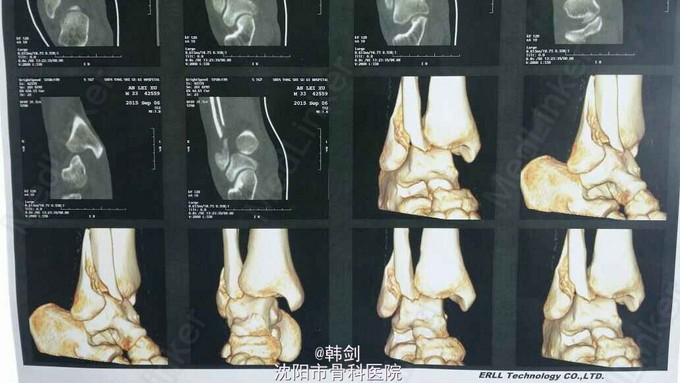

诊断:右外踝骨折伴胫距关节脱位及内侧韧带损伤。 治疗:患者入院后,完善各项检查,行手法复位,效果不佳,于9月13日行手术治疗。三维CT为复位后拍摄。

患者行“切开复位钢板内固定,内侧韧带修复铆钉固定术”。术中切开内踝后发现,内侧韧带完全断裂,从内踝间隙内取出一蝶形较大剥脱软骨快。 PS:像这种病例,请问大家,一般术前都行MR检查吗?一般这种病例,大家都行内侧韧带的修补及铆钉固定么?